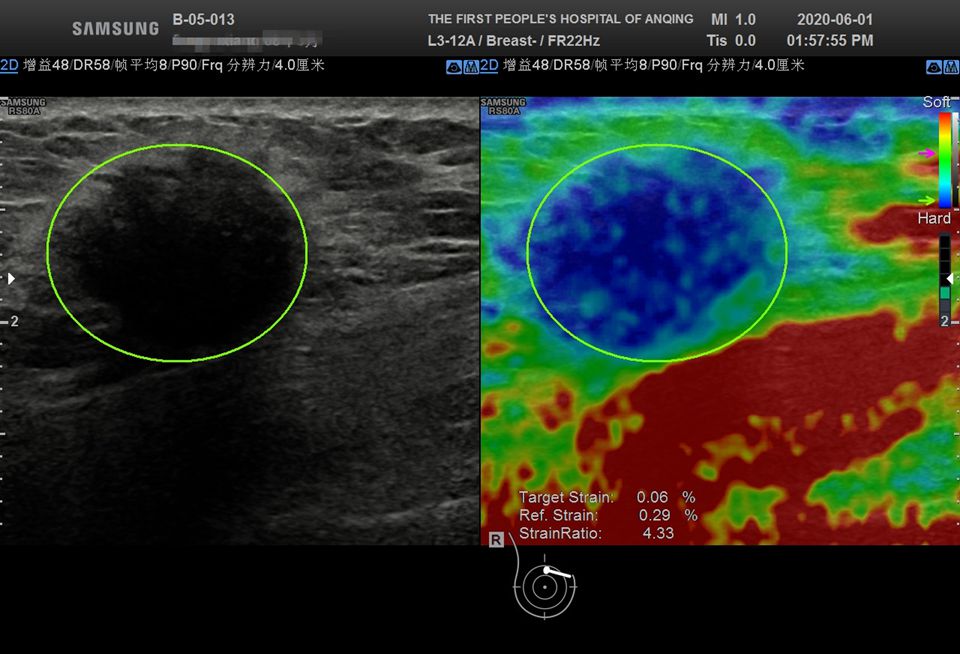

弹性成像提示:该结节为硬性结节,高度怀疑恶性